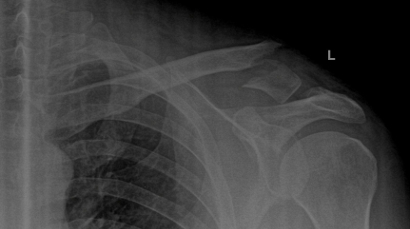

Clavicle Fracture Repair with Plate and Screws